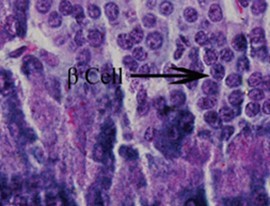

No comparable significant change observed in the mean weights of the extracted pancreas. The photomicrographs (Figure 4, Figure 5, Figure 6 and Figure 7) of the pancreatic tissue histology revealed preserved histoarchitecture in DSE and DEE groups as compared with the normal appearance of pancreas histoarchitecture from a normal healthy Wistar rat. Photomicrograph of the pancreas from diabetic control (DC) rats (Figure 7) shows distorted Islet margin with lymphocytic cells infiltration and moderate necrotic parenchyma.

Figure 4.Normal Photomicrograph of the pancreas from a non-diabetic healthy rat demonstrating normal histoarchitecture (H &E stain X400 magnification)

Figure 5.Photomicrograph of the pancreas from DEE rats showing preserved normal pancreas histoarchitecture (H &E stain X400 magnification)

Figure 6.Photomicrograph of the pancreas from DSE rats showing preserved normal pancreas histoarchitecture (H &E stain X400 magnification)

Figure 7.Photomicrograph of the pancreas from diabetic control (DC) rats showing distorted Islet margin (arrow) with lymphocytic cells infiltration and moderate necrotic parenchyma (H &E stain X400 magnification)

Due to different species of garden egg in nature, likelihood of variation in its effect on weight reduction is expected. There is an uncited claim by some nutritionists that green garden egg species works better for weight loss compared to other species. However, findings obtained in our study using the white species with green stripes (S. aethiopicum L) revealed a remarkable reduction in weight gain in diabetic rats. Though, our present study did not compare species effect on weight gain, in our subsequent research however, we shall conduct a study to correlate species and weight-lowering effect. Meanwhile, based on the present outcome of this study, recommendation of the white-with-green-striped species should be encouraged for beneficial optimal effect on weight reduction. The beneficial impacts of S. aethiopicum on glycemic status and profile are depicted in Table 3 and Figure 2. The mean FBS concentrations decreased significantly (P < 0.05) in both DEE and DSE groups (DEE >> DSE, P = 0.025) compared with the control. The observed difference in their values was similar in manner to its effect on weight gain. The glycemic tolerance improved remarkably in both groups. This antidiabetic potential may be attributed to a major phenolic compound called chlorogenic acid (5-O-caffeoyl-quinic acid; CGA) present in garden egg 13, 21. Bhaskar 13 and Plazas 21 studies revealed that chlorogenic acid possessed anti-obesity, anti-inflammatory, anti-diabetic and, cardio-protective properties. The incremental areas under the glycemic response curves of DEE and DSE rats decreased remarkably compared with the control (Figure 2). The postprandial glycemic response peaked at 30 minutes of glucose challenge in both groups. The TC, TG and LDL-C concentrations decreased significantly with corresponding significant increase in HDL concentration in DEE and DSE rats (Figure 3). However, the extract impacts more beneficial antilipidemic effect than the supplemented diet. This finding also suggests that the optimal antilipidemic effect can be derived when S. aethiopicum is consumed in fresh or raw form than in mixed meal. The antilipaemic effect of eggplants has been attributed to an important phytonutrient compound called anthocyanin found in abundance in the skin of the eggplant which was reported to improve lipid profile through lipid peroxidation and serum antioxidants concentrations increase 27. Besides this antilipaemic activity, anthocyanin has also been reported to play significant role against diabetes, neuronal problems, cardiovascular disorders, and cancer as well 30. The pancreatic tissues sections’ photomicrographs examined under high power magnification (x 400) light microscope revealed the effects of S. aethiopicum on pancreas histoarchitecture. Figure 4 shows the normal appearance of the pancreatic histoarchitecture obtained from a healthy non-diabetic Wistar rat. Comparison of the experimental grouped rats photomicrographs with the normal revealed that the histoarchitecture of the pancreas in DEE and DSE (Figure 5, Figure 6) rats were preserved with no visible pathologic changes while the photomicrograph of the pancreas from diabetic control (DC) rats (Figure 7) shows distorted Islet margin with lymphocytic cells infiltration and moderate necrotic parenchyma. Examining the histological consequence of any product prior to recommendation is very essential because histological analysis of target organs for pathological changes surveillance is necessary to enhance screening assessment of quality and safety of product prior to recommendation for human consumption 31